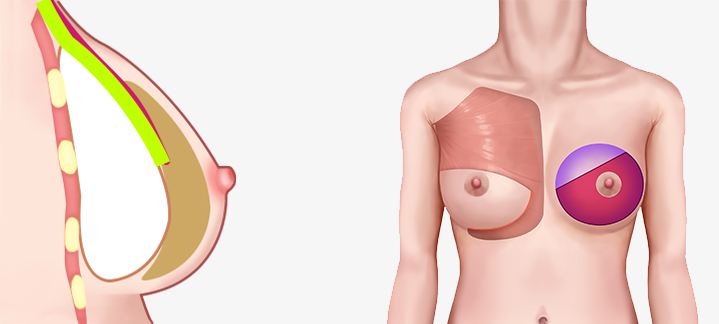

เทคนิคแบบ Dual Plane แบ่งออกเป็น 3 ประเภทใหญ่ ๆ ขึ้นอยู่กับระดับของการสร้างพื้นที่ใต้เยื่อหุ้มเซลล์

โดยเสริมซิลิโคนที่ด้านบนของกล้ามเนื้อและด้านล่างของเนื้อเยื่อ ทำให้มีลักษณะคล้ายกับซิลิโคนมากที่สุด

สามารถสร้างรูปร่างของหน้าอกได้ การเคลื่อนย้ายของซิลิโคนหรือรูปร่างของหน้าอกจะไม่เปลี่ยนแปลง

โดยเสริมซิลิโคนใต้กล้ามเนื้อ และเหนือกล้ามเนื้อ อัตราการเกิดการสร้างทรงกลมต่ำกว่าการเสริมแบบมีสายมาก

สามารถสร้างสัมผัสตามธรรมชาติและเส้นใต้เต้านมได้ การเปลี่ยนแปลงรูปร่างมีน้อย

วิธีการใส่ท่อนบนของซิลิโคนลงไปใต้กล้ามเนื้อ และท่อนล่างลงไปใต้เยื่อกล้ามเนื้อ

มักจะใช้กล้ามเนื้อปิดเนื้อเยื่อบางๆของผิวหนัง เพื่อให้เห็นซิลิโคน และความกังวลน้อยลง

เนื่องจากความกดดันของกล้ามเนื้อ จึงมีความเสี่ยงน้อยที่ตำแหน่งของซิลิโคนจะเคลื่อนที่ได้ และความน่าจะเป็นที่จะเกิดคลื่นริ้วรอยก็มีน้อยด้วย

บริเวณที่มีกล้ามเนื้อจะมีผิวหนังและเนื้อเยื่ออ่อนที่ยืดไม่ค่อยออก แต่บริเวณที่ไม่มีกล้ามเนื้อปกคลุมนั้นค่อนข้างที่จะ

ผิวหนังและเนื้อเยื่อที่เชื่อมต่อกันจะยืดได้ดีและช่วยให้เส้นโค้งธรรมชาติยังคงอยู่แม้ในกรณีที่ด้านล่างของหน้าอกแน่นมาก

วิธีการใส่ซิลิโคนบนกล้ามเนื้อ ,ใส่ซิลิโคนใต้เนื้อเยื่อ

เป็นวิธีการผ่าตัดที่เสริมข้อเสียของวิธีใช้สายเดรนและวิธีใช้กล้ามเนื้อ และรวมข้อดีเข้าด้วยกัน

เป็นวิธีการผ่าตัดสามารถสร้างรูปร่างตามธรรมชาติได้

เทคนิคแบบ Dual Plane กล้ามเนื้อหดตัวลงและเคลื่อนที่ขึ้น

ผิวหนังและเนื้อเยื่อที่เชื่อมต่อกันค่อนข้างยืดได้ดี จึงสามารถสร้างเส้นโค้งตามธรรมชาติได้